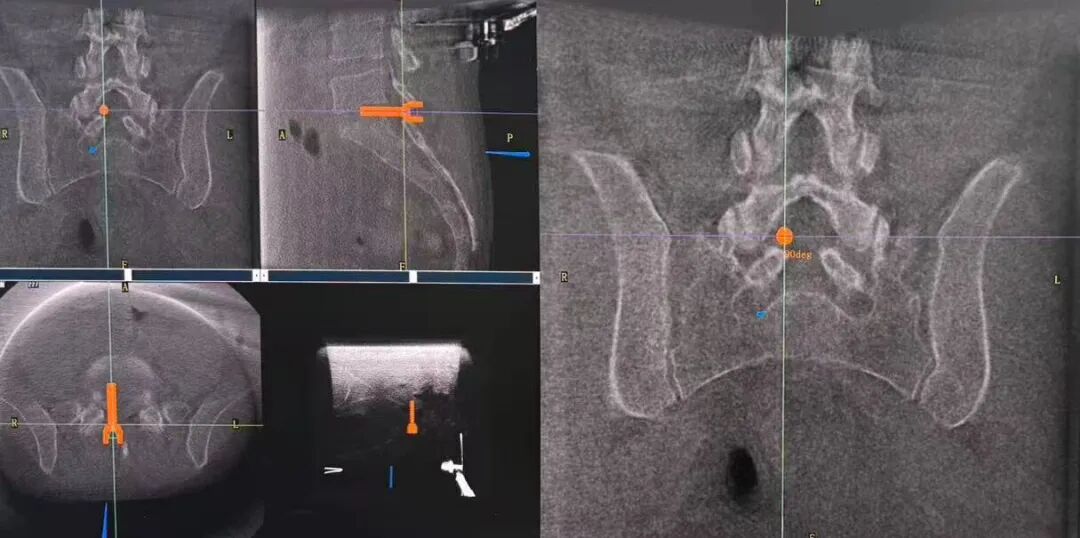

手术过程中,平板三维C形臂重建的高清三维影像,将患者腰椎的解剖结构、病灶位置等细节清晰呈现。机器人机械臂根据医生预设手术路径自动定位导向,医生依托椎间孔镜技术,仅在患者体表做1-2厘米的微小切口建立工作通道,精准摘除突出髓核、松解神经根,全程微创,确保了整个手术过程安全、高效。

精准路径规划